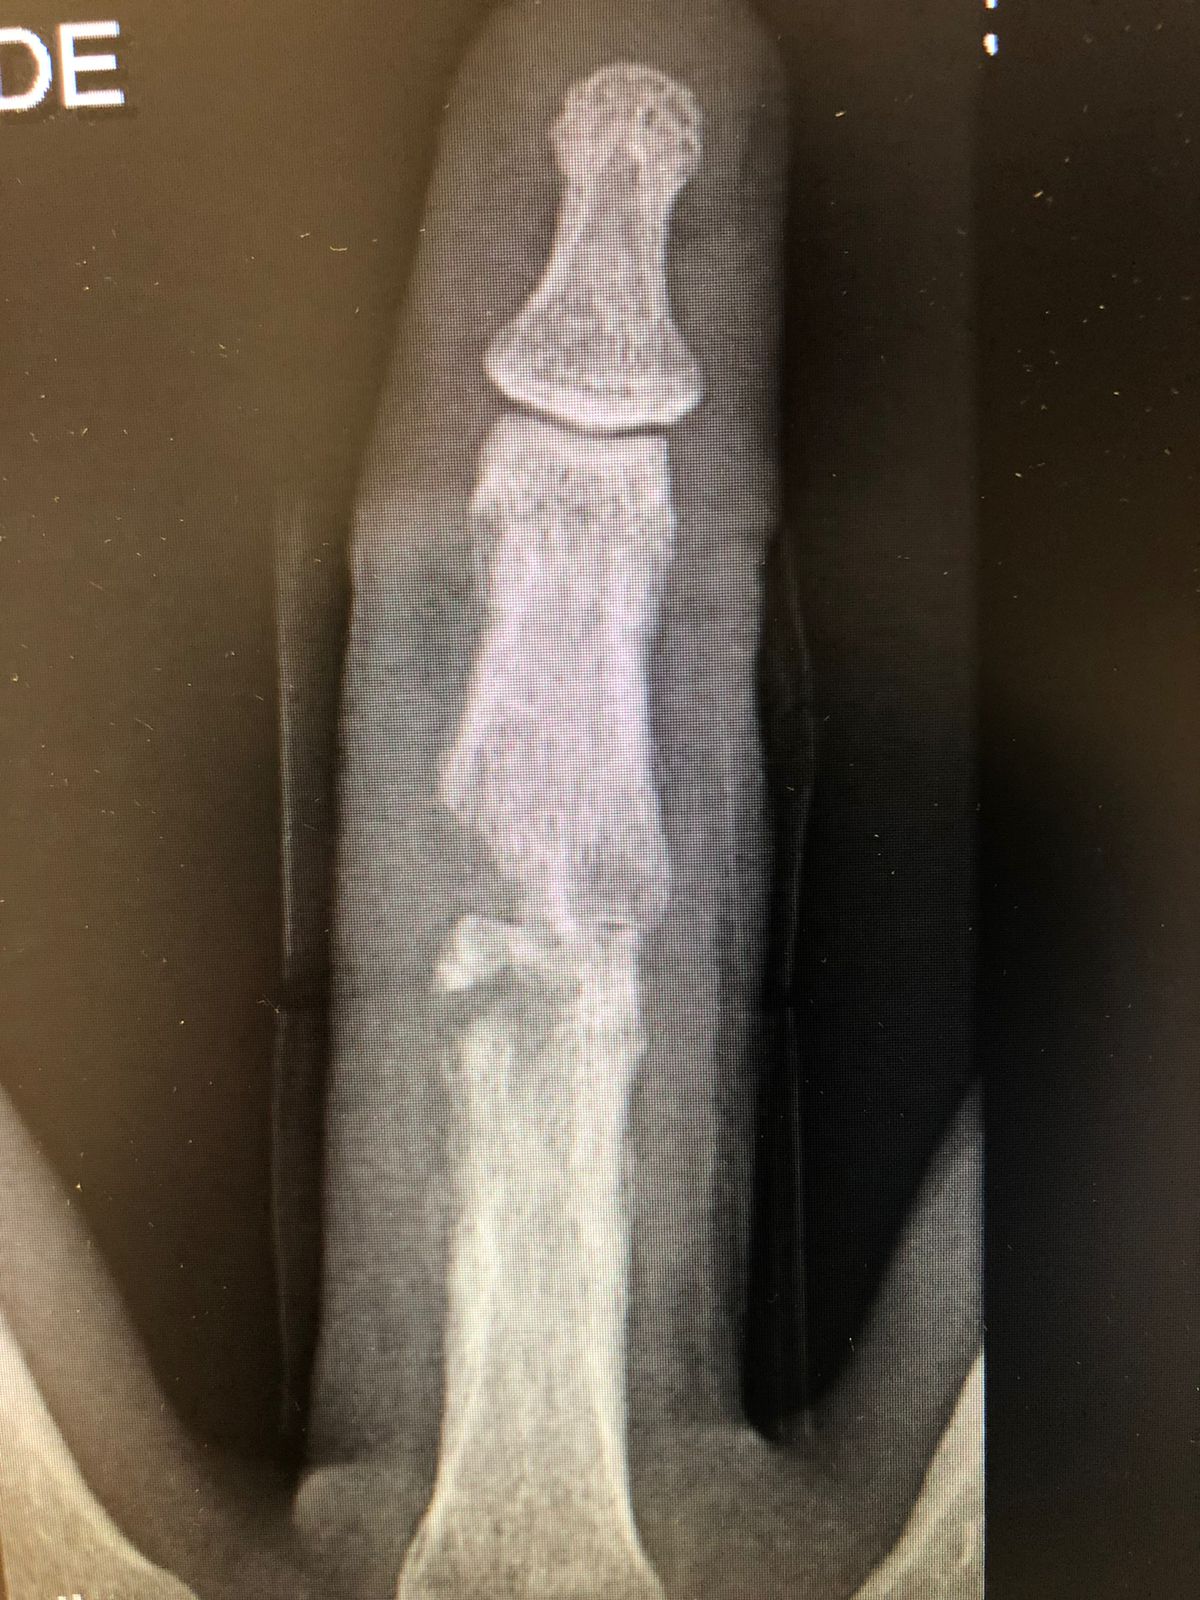

🧪 Diagnóstico

• Radiografia (alterações tardias)

osteomielite por mordedura